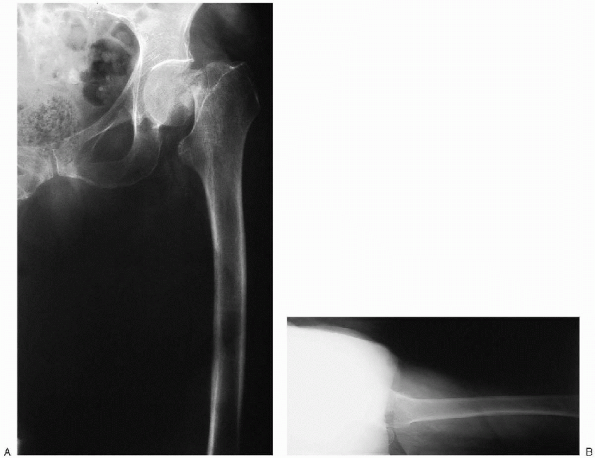

FIGURE 22-3. Anteroposterior radiograph of the pelvis demonstrates a displaced, left femoral neck fracture.

Anteroposterior view of the pelvis (Fig. 22-3)

Anteroposterior and cross-table lateral view of the involved proximal femur (Fig. 22-4)

FIGURE 22-4. Anteroposterior (A) and lateral cross-table (B) views of the left hip demonstrate a displaced femoral neck fracture.